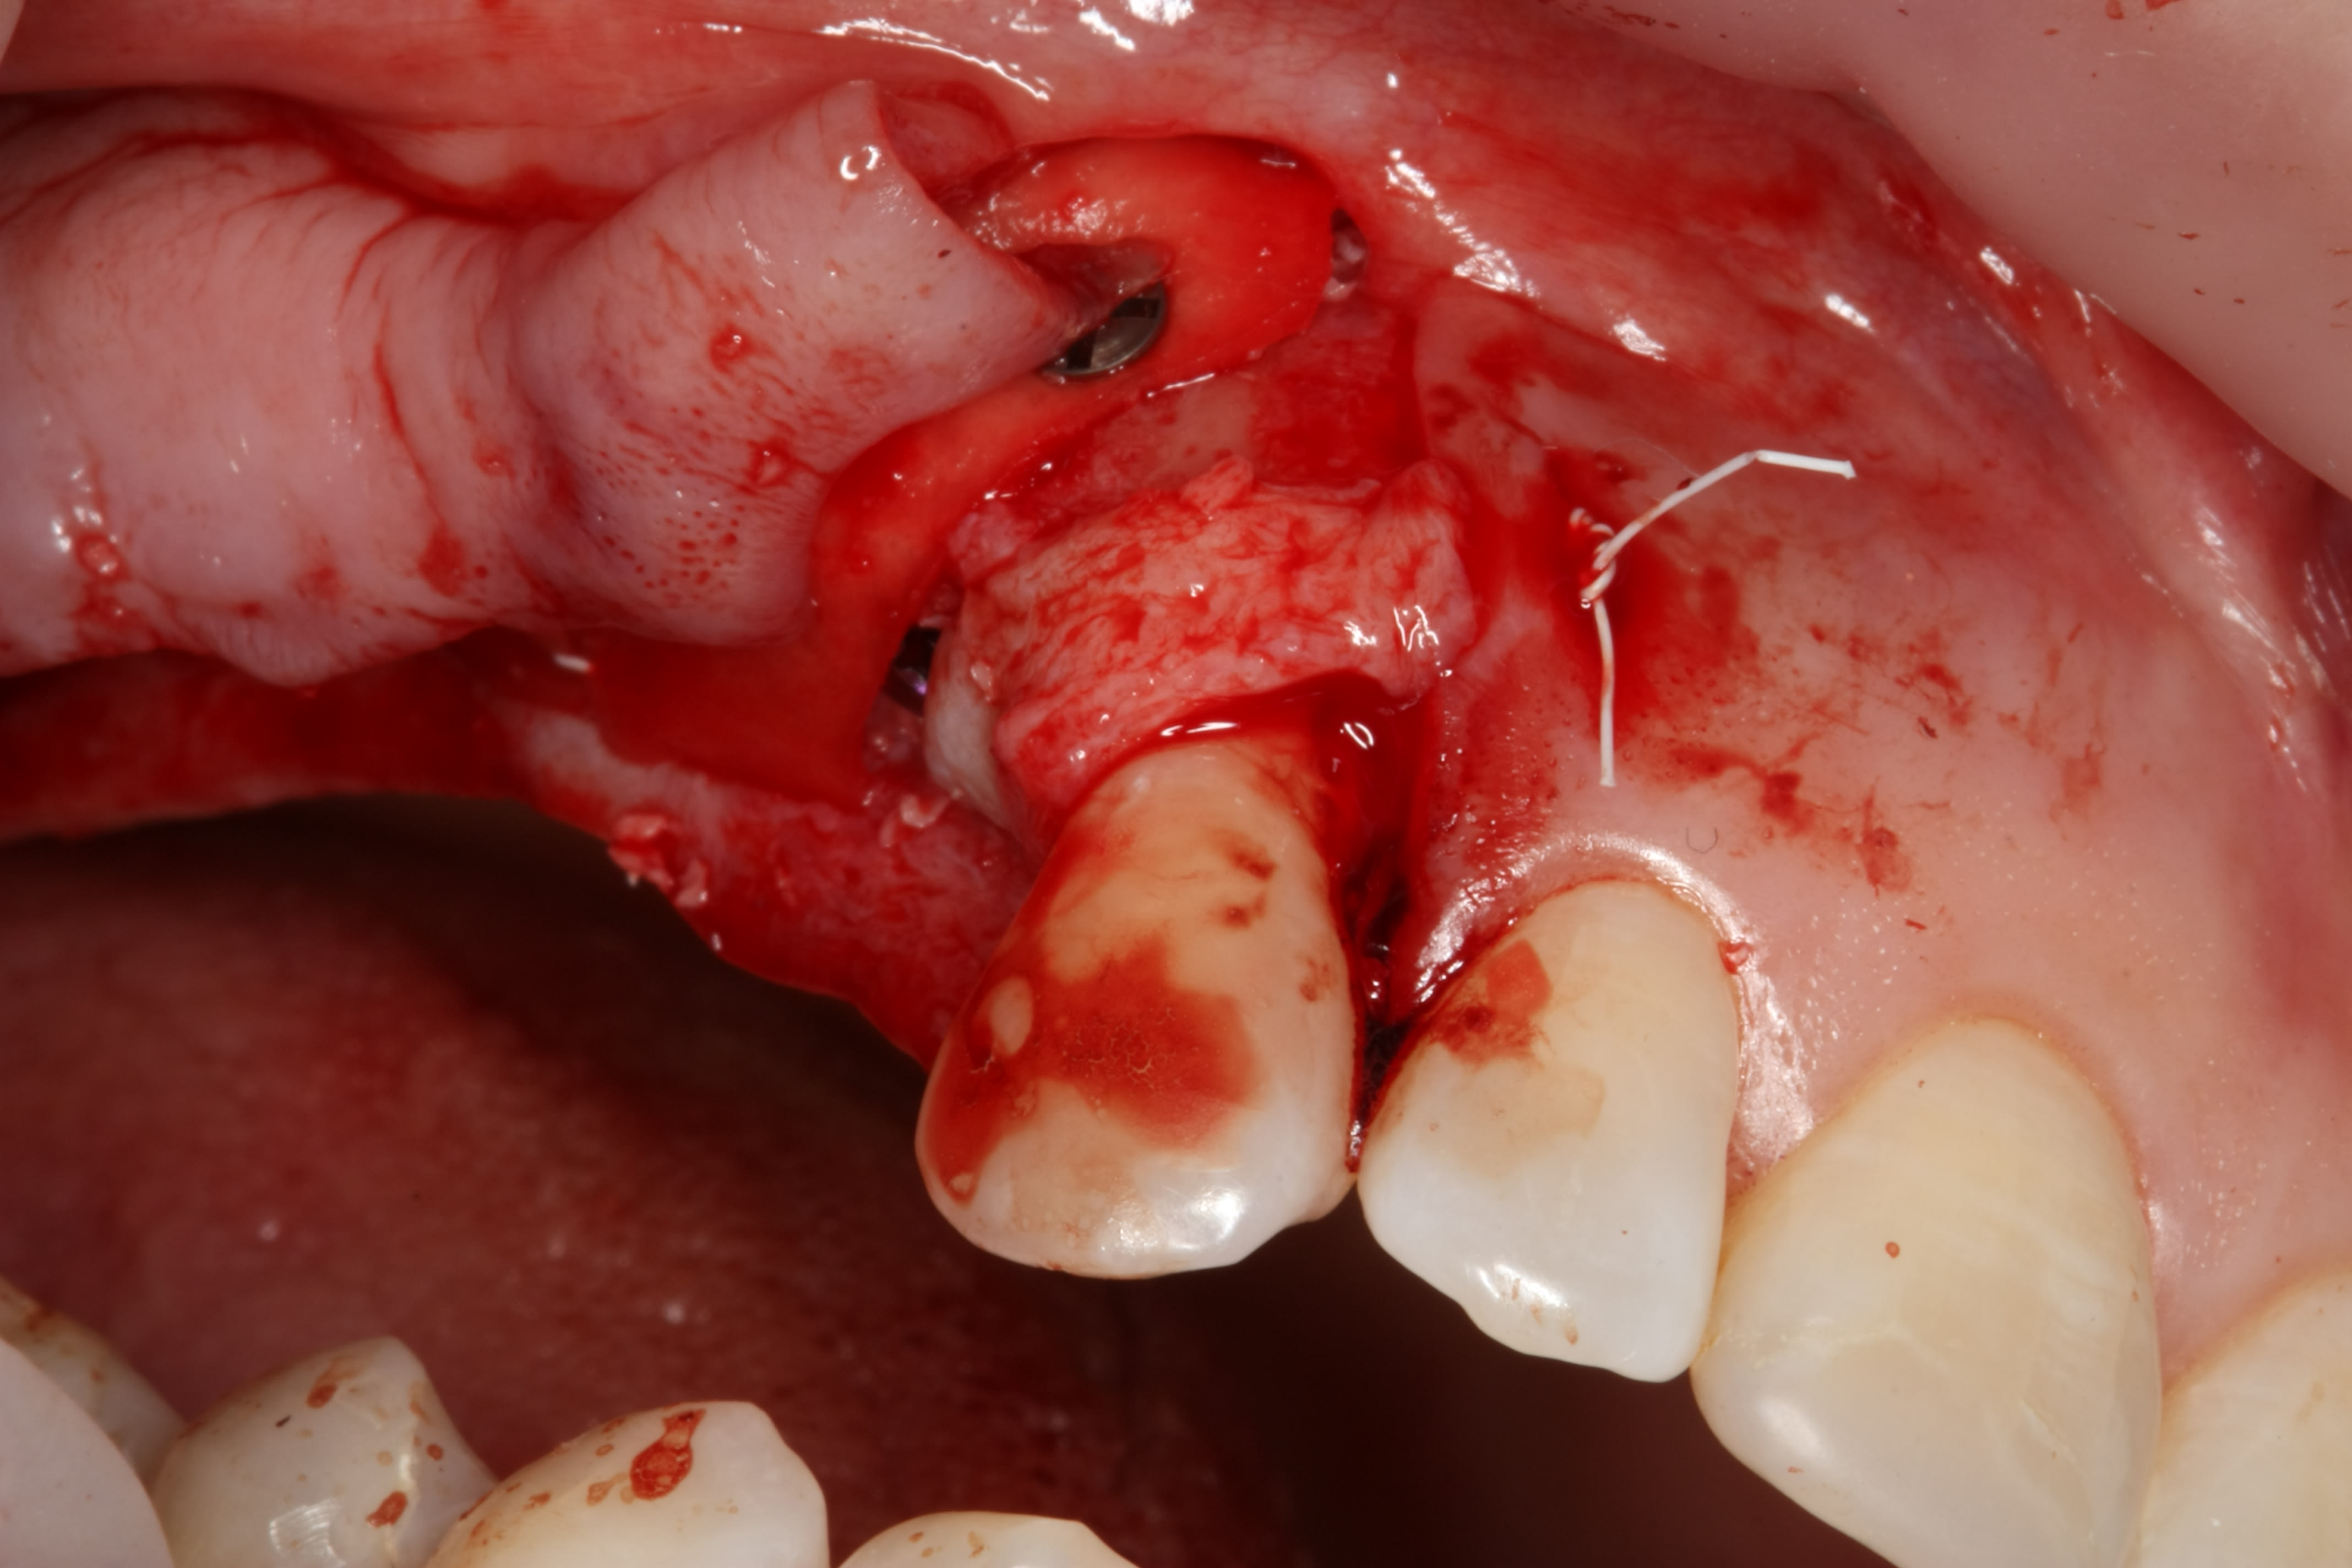

Exo racine région 15

Greffe/expansion zone 14 (que 3 mm d'os au départ)

Pose implants 14-15-16 (il n'y a pas de 7 en bas)

Greffe d'os zone 14-15 (particules, membrane collagène)

Un peu de mucco entre 14-13 (conjonctif)